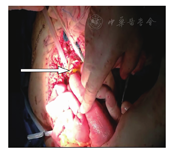

沿原切口逐层进入腹腔,探查移植胰腺及十二指肠血供良好,无血栓及狭窄,与周围组织无明显粘连。胰腺表面少量脂肪皂化,胰腺组织无坏死和渗出;移植胰十二指肠与空肠吻合口可见多个针眼裂开,部分肠液渗出(图1),输出袢因粘连部分成角,吻合口以上输入空肠扩张,腹腔内少量脓性积液,腹腔轻度污染,余肠道未见明显扭转等病变,大量温生理盐水冲洗干净,决定行移植胰空肠Roux-en-Y吻合术。沿原吻合口输入袢系膜分离,结扎保留输入、输出袢血管血供,距输入袢吻合口约1.5 cm,直线切割器切断空肠,输入袢肠管残端1#丝线加固包埋。拆除原吻合口缝线及缝钉,清除表面缝线吻合钉及瘢痕组织,4#缝线间断行移植胰腺十二指肠与受者的空肠(输出袢)侧侧吻合;距离吻合口约50 cm输入袢与受者空肠端侧吻合,方法同上,距离该吻合口约15 cm,开0.5 cm小口,留置F12空肠营养管,肠道包埋,经皮引出。同法留置移植胰腺肠道造瘘管,就近经皮引出固定,大量温生理盐水冲洗三遍,查创面无明显渗血后,留置右侧胰周、左侧胰周、胰后及盆腔引流管,缝合腹壁各层术中岀血约200 ml。